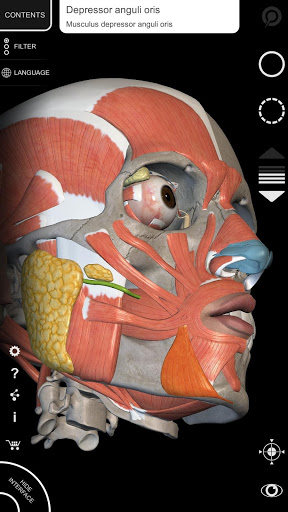

"Anatomy 3D Atlas" cho phép bạn nghiên cứu giải phẫu người theo cách dễ dàng và tương tác.

Thông qua giao diện đơn giản và trực quan, bạn có thể quan sát mọi cấu trúc giải phẫu từ mọi góc độ.

Các mô hình giải phẫu 3D đặc biệt chi tiết và có kết cấu lên đến độ phân giải 4k.

MÔ HÌNH GIẢI PHẪU 3D

• Hệ thống cơ xương